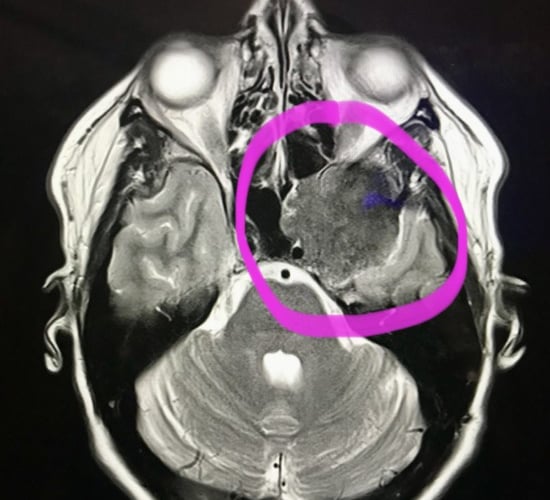

Magda has been a long-time supporter of Wear A Hat Day and Brain Tumour Research as she herself was diagnosed with meningioma - a non-cancerous brain tumour - six years ago. In 2023, she raised £345 for the charity and, in a previous year, held a Wear A Hat Day event and “Best Hat” competition, with her children picking the winner.

Magda’s diagnosis came after years of unrecognised symptoms, including vision problems, migraines, and eventually tinnitus, which were initially attributed to other causes until scans identified the tumour. She underwent 11 hours of surgery at Southmead Hospital in Bristol in March 2021 and spent a week recovering in hospital. Her family were unable to visit during this time due to Covid restrictions.

Due to the location of the tumour, surgeons are unable to remove the tumour completely, so Magda undergoes annual MRI scans to monitor the remaining tumour and remains committed to raising awareness and supporting others affected.